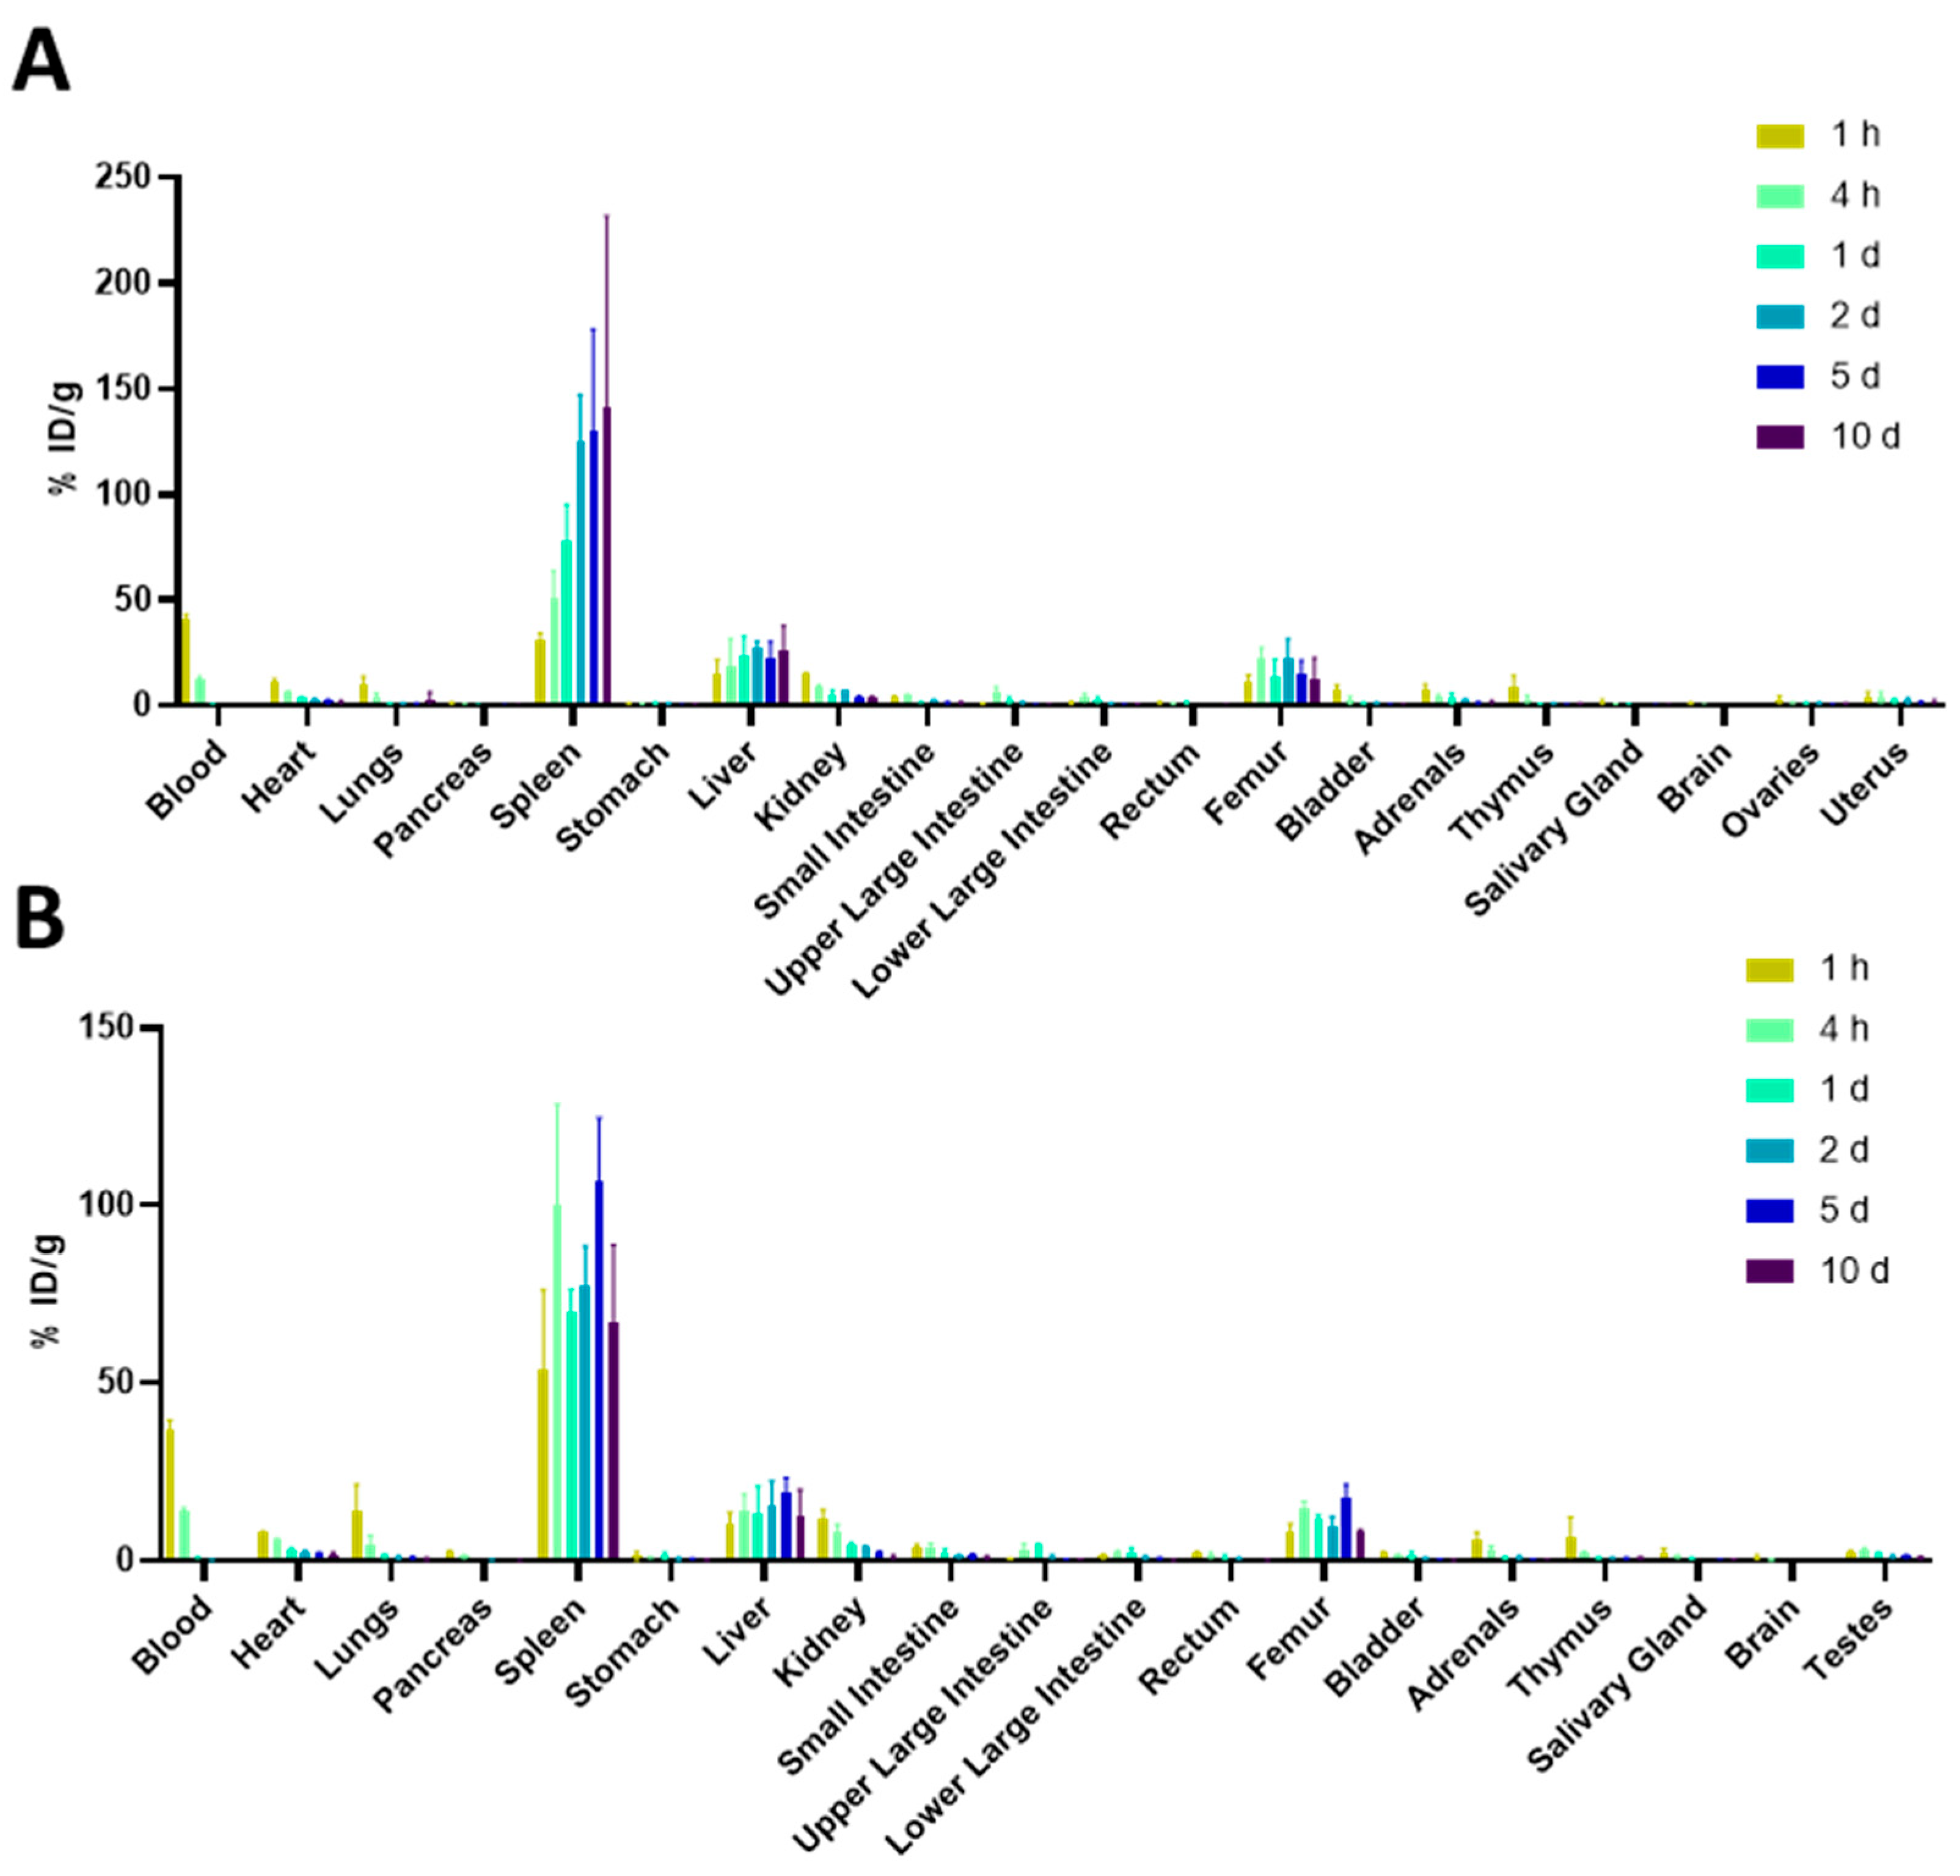

2. Results